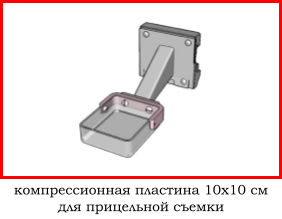

4.2 обычно отсутствует возможность прицельной съемки (специальная компрессионная пластина квадратной или округлой формы),

4.2 наличие принадлежностей для прицельной съемки,

В зависимости от высоты устройства достигается коэффициент геометрического увеличения объекта исследования 1.5х, 1.8х или 2.0х.

Метод прицельной маммографии с увеличением применяется для более детального исследования определенной области молочной железы. Он отличается высокой точностью диагностики. В отличие от обычной маммографии, которая предоставляет более общую информацию о состоянии молочных желез, прицельная маммография с увеличением позволяет получить точные данные о процессах, происходящих в тканях, благодаря методу компрессии конкретного участка.